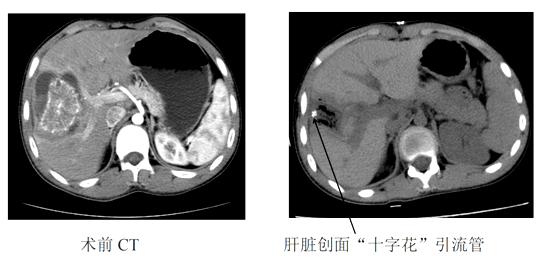

州人民医院外二科喻定刚主任医师在认真阅读术前CT片后,考虑患者门静脉右前叶分支受侵犯,无法保留,为减少术后并发症,拟定行解剖性右前肝叶切除术,即精准解剖性Ⅴ+Ⅷ段切除术。2019年03月26日,经过充分的术前准备,由喻定刚主任医师主刀、罗斯满副主任医师和陈见中主治医师共同为患者在全麻下进行了解剖性肝Ⅴ段、Ⅷ段切除术,手术顺利,全程手术时间约4小时,患者在术中出血仅为400ml。术后3天复查CT(切效果良好)。